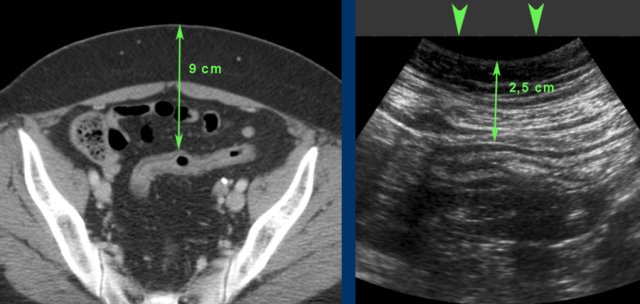

CT of an obese patient with inactive ulcerative colitis. The sigmoid lies 9 cms from the skin.

During compression (arrowheads) this distance was decreased to 2.5 cms allowing the use of a high frequency probe.